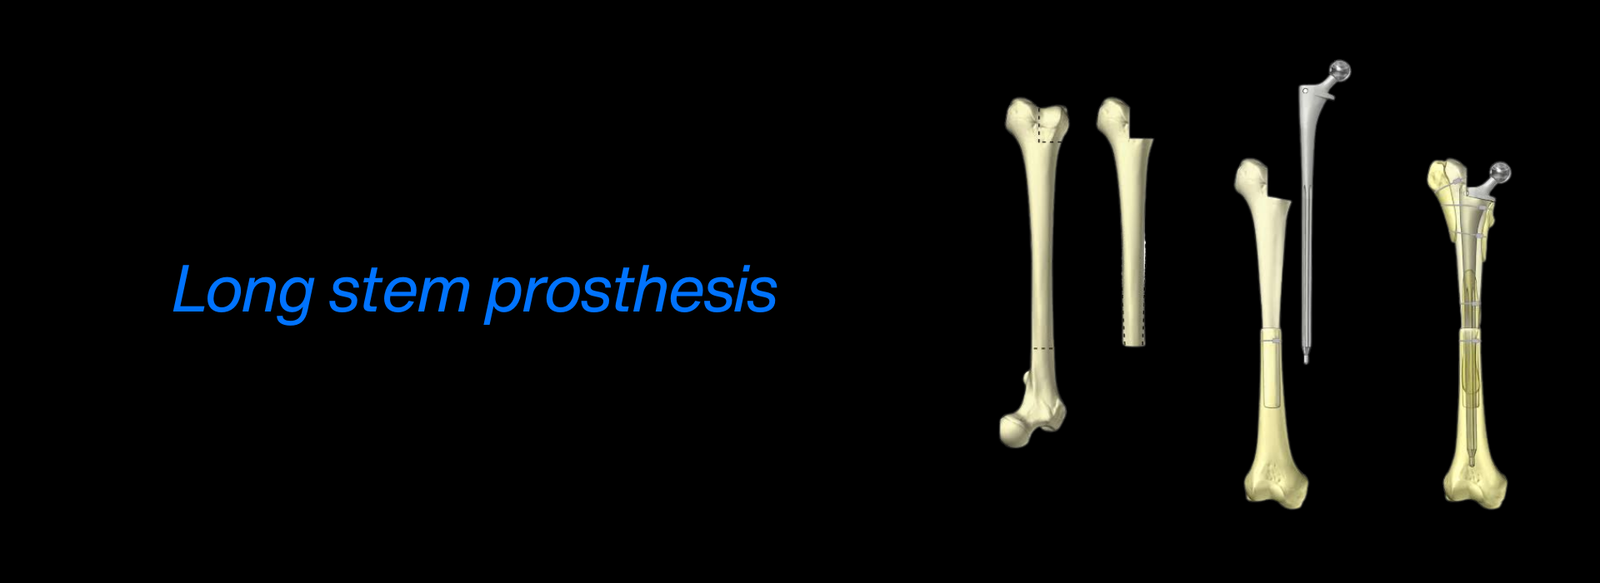

Fellowship in Arthroplasty: Specializing in joint replacement surgery, including procedures like hip and knee replacement. Arthroplasty is essential for patients with joint diseases or severe trauma where joint function must be restored.

AO Recon Hip & Knee Arthroplasty: Advanced training in reconstructive surgeries, particularly hip and knee replacements, for patients suffering from degenerative diseases or complex injuries.